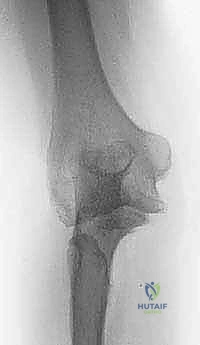

| الأشعة السينية العادية (X-Rays) | تقييم الهيكل العظمي الأساسي، الكشف عن الكسور القديمة، المسامير والشرائح السابقة، ومدى تآكل المفصل. | كخطوة أولى وأساسية في جميع الحالات. وتؤخذ من زوايا متعددة. |

| الأشعة المقطعية (CT Scan) مع بناء ثلاثي الأبعاد 3D | توفير تفاصيل دقيقة للغاية عن شكل العظام، التكلسات المغايرة، التئام الكسور، وتخطيط حجم ونوع المفصل الصناعي أو الشرائح المطلوبة. | ضروري جداً قبل التخطيط لجراحات التبديل الكلي للكوع أو إزالة التكلسات العظمية الضخمة. |